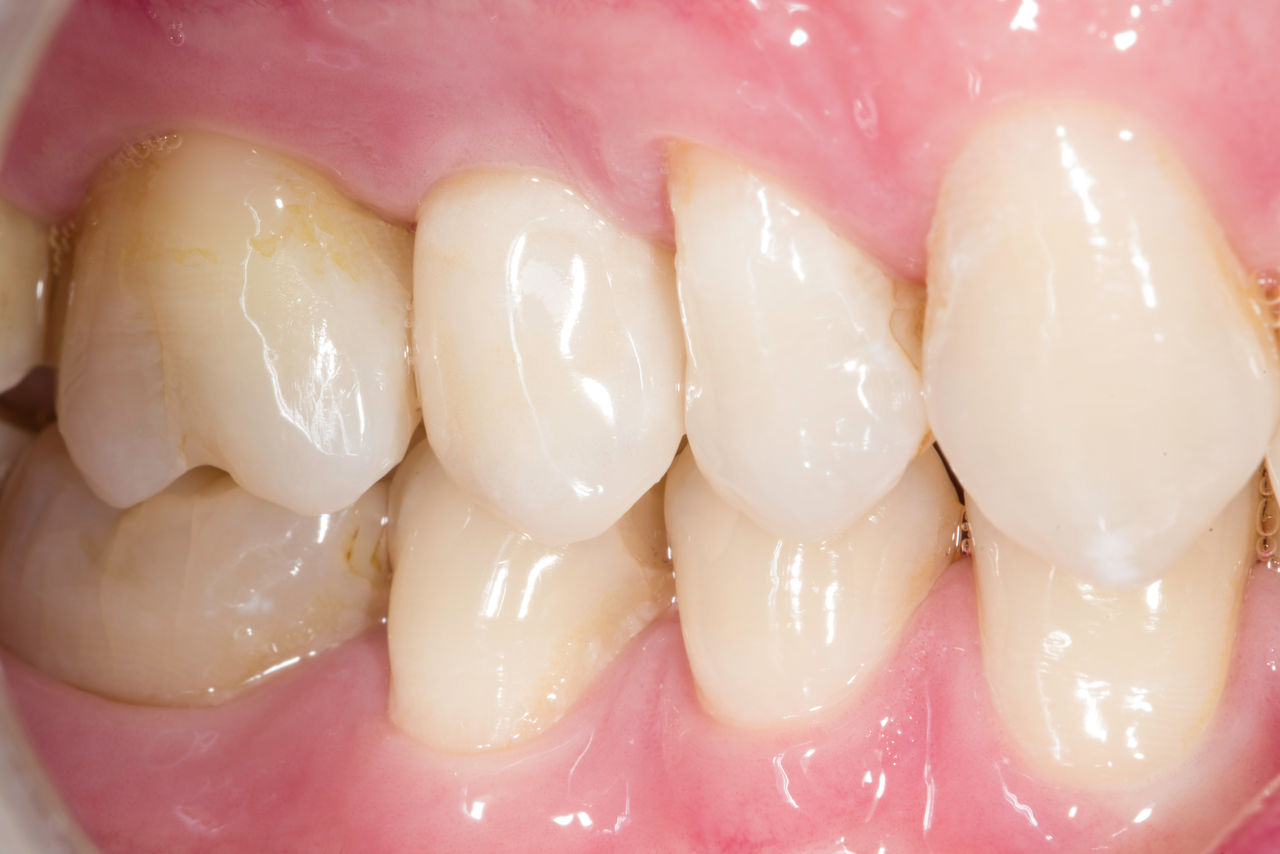

Upper central incisors, in 4 hours

Four IPS e.max CAD single crowns

The restoration with all-ceramic crowns did not require subgingival preparation to cover the margin and no dark metal shadows disturbed the aesthetics. With CEREC Primescan and CEREC Primemill patients receive a high-quality all-ceramic restoration faster than ever before.

Before: Inadequate fillings on teeth 12-22, an uneven gingival line on 12 and 11 and incisal edges severely eroded.

After: Four highly aesthetic and individualised lithium disilicate ceramic crowns.

Claudia Scholz

Kiel, Germany